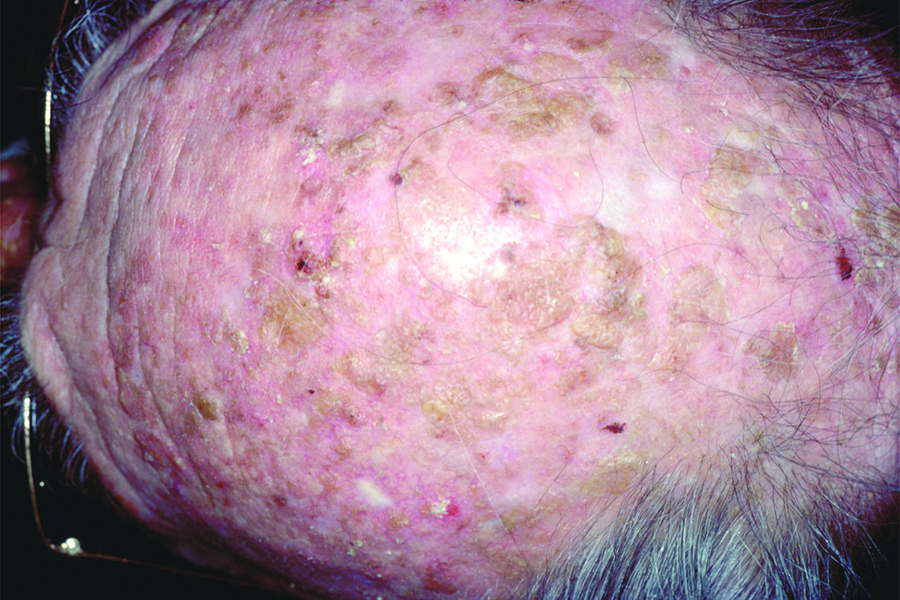

Actinic Keratosis (AK) Photos

Actinic keratosis on head or neck. Photo: International Skin Imaging Collaboration at isic-archive.com

Squamous cell carcinoma on the head. Photo: International Skin Imaging Collaboration at isic-archive.com

Squamous cell carcinoma on the head. Photo: International Skin Imaging Collaboration at isic-archive.com